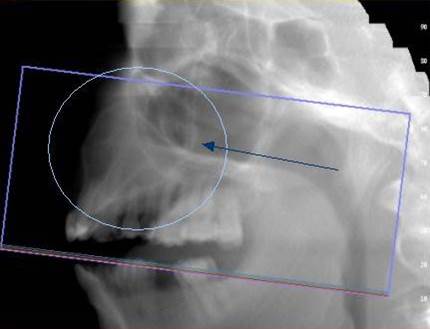

3D DVT - NewTom

Je speciální zubní digitální tříprostorový tomograf (3D), který umožňuje na základě jediného

snímkování vytvořit všechny typy RTG zobrazení, které jsou pro lékaře potřebné. Díky používané technologii tzv. „kuželového paprsku“ a speciálním senzorům je

výrazně zmenšená dávka záření - o více jak 80% proti klasickému CT vyšetření. To je významné zejména u dětí. Pomocí tohoto přístroje je možné zjisti skutečnou situaci v čelistních kostech pacienta tedy množství kosti - můžeme změřit skutečnou šířku i výšku kosti, i kvalitu kosti (hustotu) v místě uvažované implantace. 3D (tříprostorové) zobrazení umožňuje zvýšit prostorovou představu operatéra ještě před vlastní operací a zároveň pacientovi lépe objasnit a ukázat oblast plánovaného zavedení implantátu.

Pacient „neumí číst“ RTG snímky, ale díky 3D zobrazení vidí „svoji skutečnou čelist“

- např. jak je nízká či úzká, vidí průběh nervu nebo velikost čelistní dutiny, což mu umožní i pochopení nutnosti v některých případech provést pomocné zákroky ještě před vlastním zavedením implantátu (viz. kostní štěp, sinus lift, kostní granulát...).